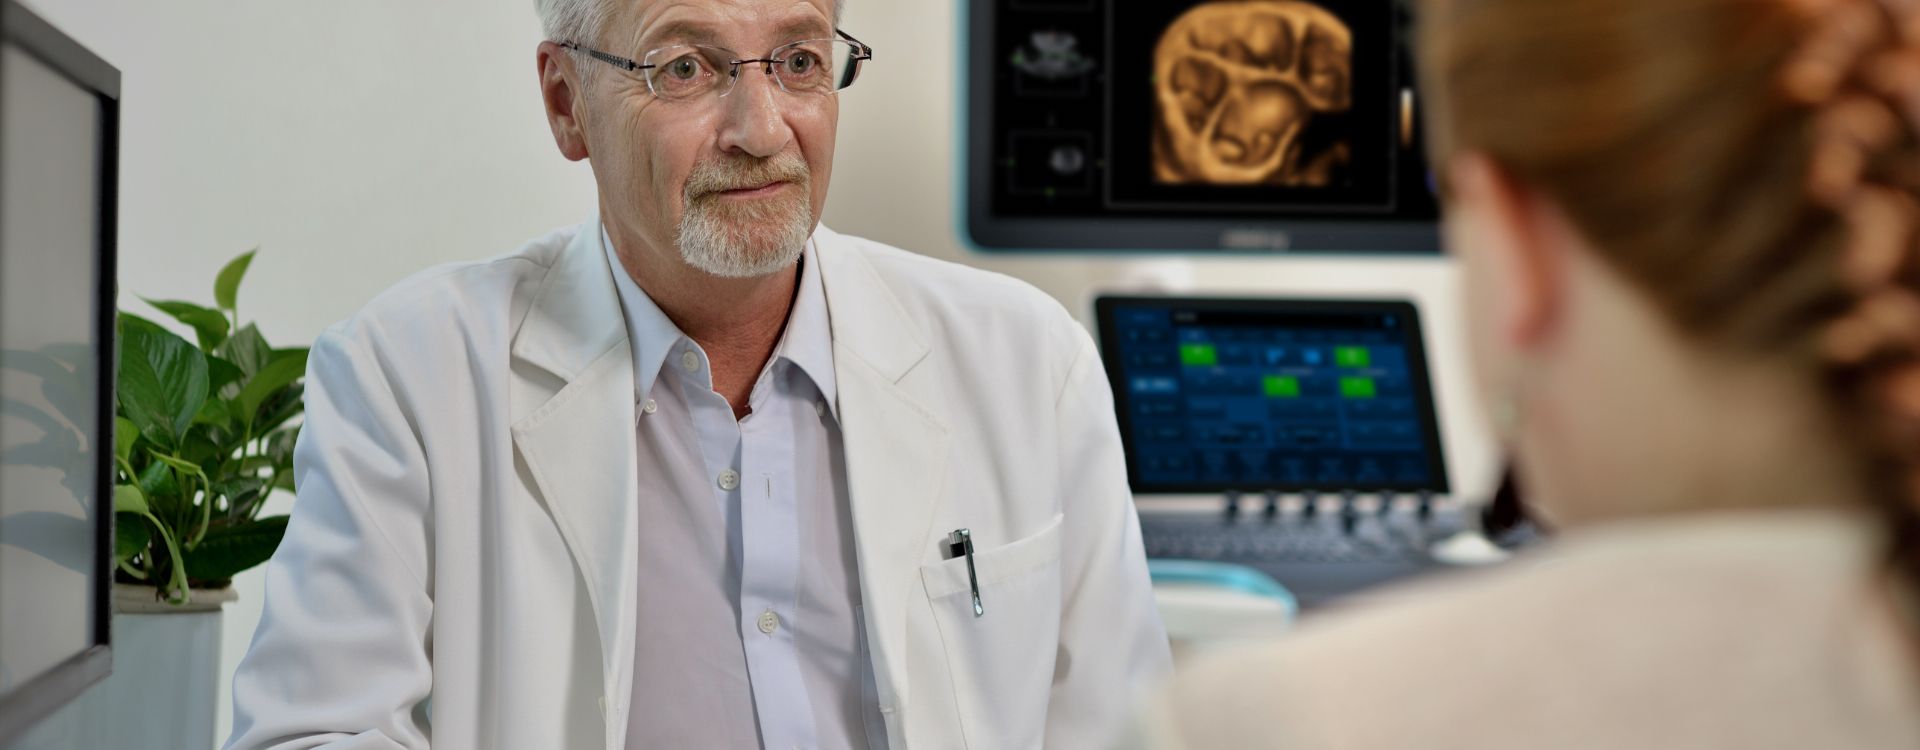

Precyzja buduje pewno??

Aparaty ultrasonograficzne z serii Resona, dzi?ki szerokiej gamie za pomoc? wszechstronnych sond do r√≥?nych zastosowaŇĄ i wydajnych narz?dzi do zastosowaŇĄ klinicznych, pomagaj? U?ytkownikom stawia? dok?adniejsz? i efektywniejsz? diagnoz? oraz ocenia? wyniki.

Produkty do obrazowania ogólnego